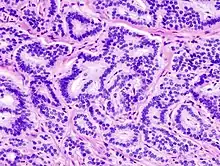

Histológicamente, las células del tumor carcinoide se reconocen por su capacidad de captar o reducir las sales de plata, es decir, son argirófilas o argentafines y específicamente tienen un potencial endocrino al poder secretar especialmente serotonina o 5-hidroxitriptamina (su metabolito en orina es el ácido 5-indolacético), así como 5-hidroxitriptófano, calicreínas, histamina, prostaglandinas, ACTH, insulina, MSH, catecolaminas, PTH, gonadotropinas y sustancia P.[1][7]

En una visión al microscopio óptico, nos encontramos un tumor formado por células pequeñas con núcleo central, escasas mitosis y un citoplasma con gránulos; además de vasos que irrigan la tumoración. Sugiere que tiene origen en células pluripotenciales. Las células argirófilas presentan positividad al reactivo Grimelius y Sevier-Mayer. Ultraestructuralmente, las células poseen unos gránulos secretores en su membrana. Inmunohistoquímicamente, se produce una gran variabilidad pero, en general, presentan una reacción positiva a la queratina, serotonina, enolasa neuroespecífica, cromogranín A y B, secretoneurina, sinaptofisina, Leu-7 y neurofilamentos. Además, se han detectado hormonas peptídicas del tipo de la somatostatina, bombesina, péptido relajador de la gastrina, péptido relajador de la hormona del crecimiento, gastrina, polipéptido pancreático, VIP y calcitonina; excepcionalmente se ha observado también melanina.[1][2]